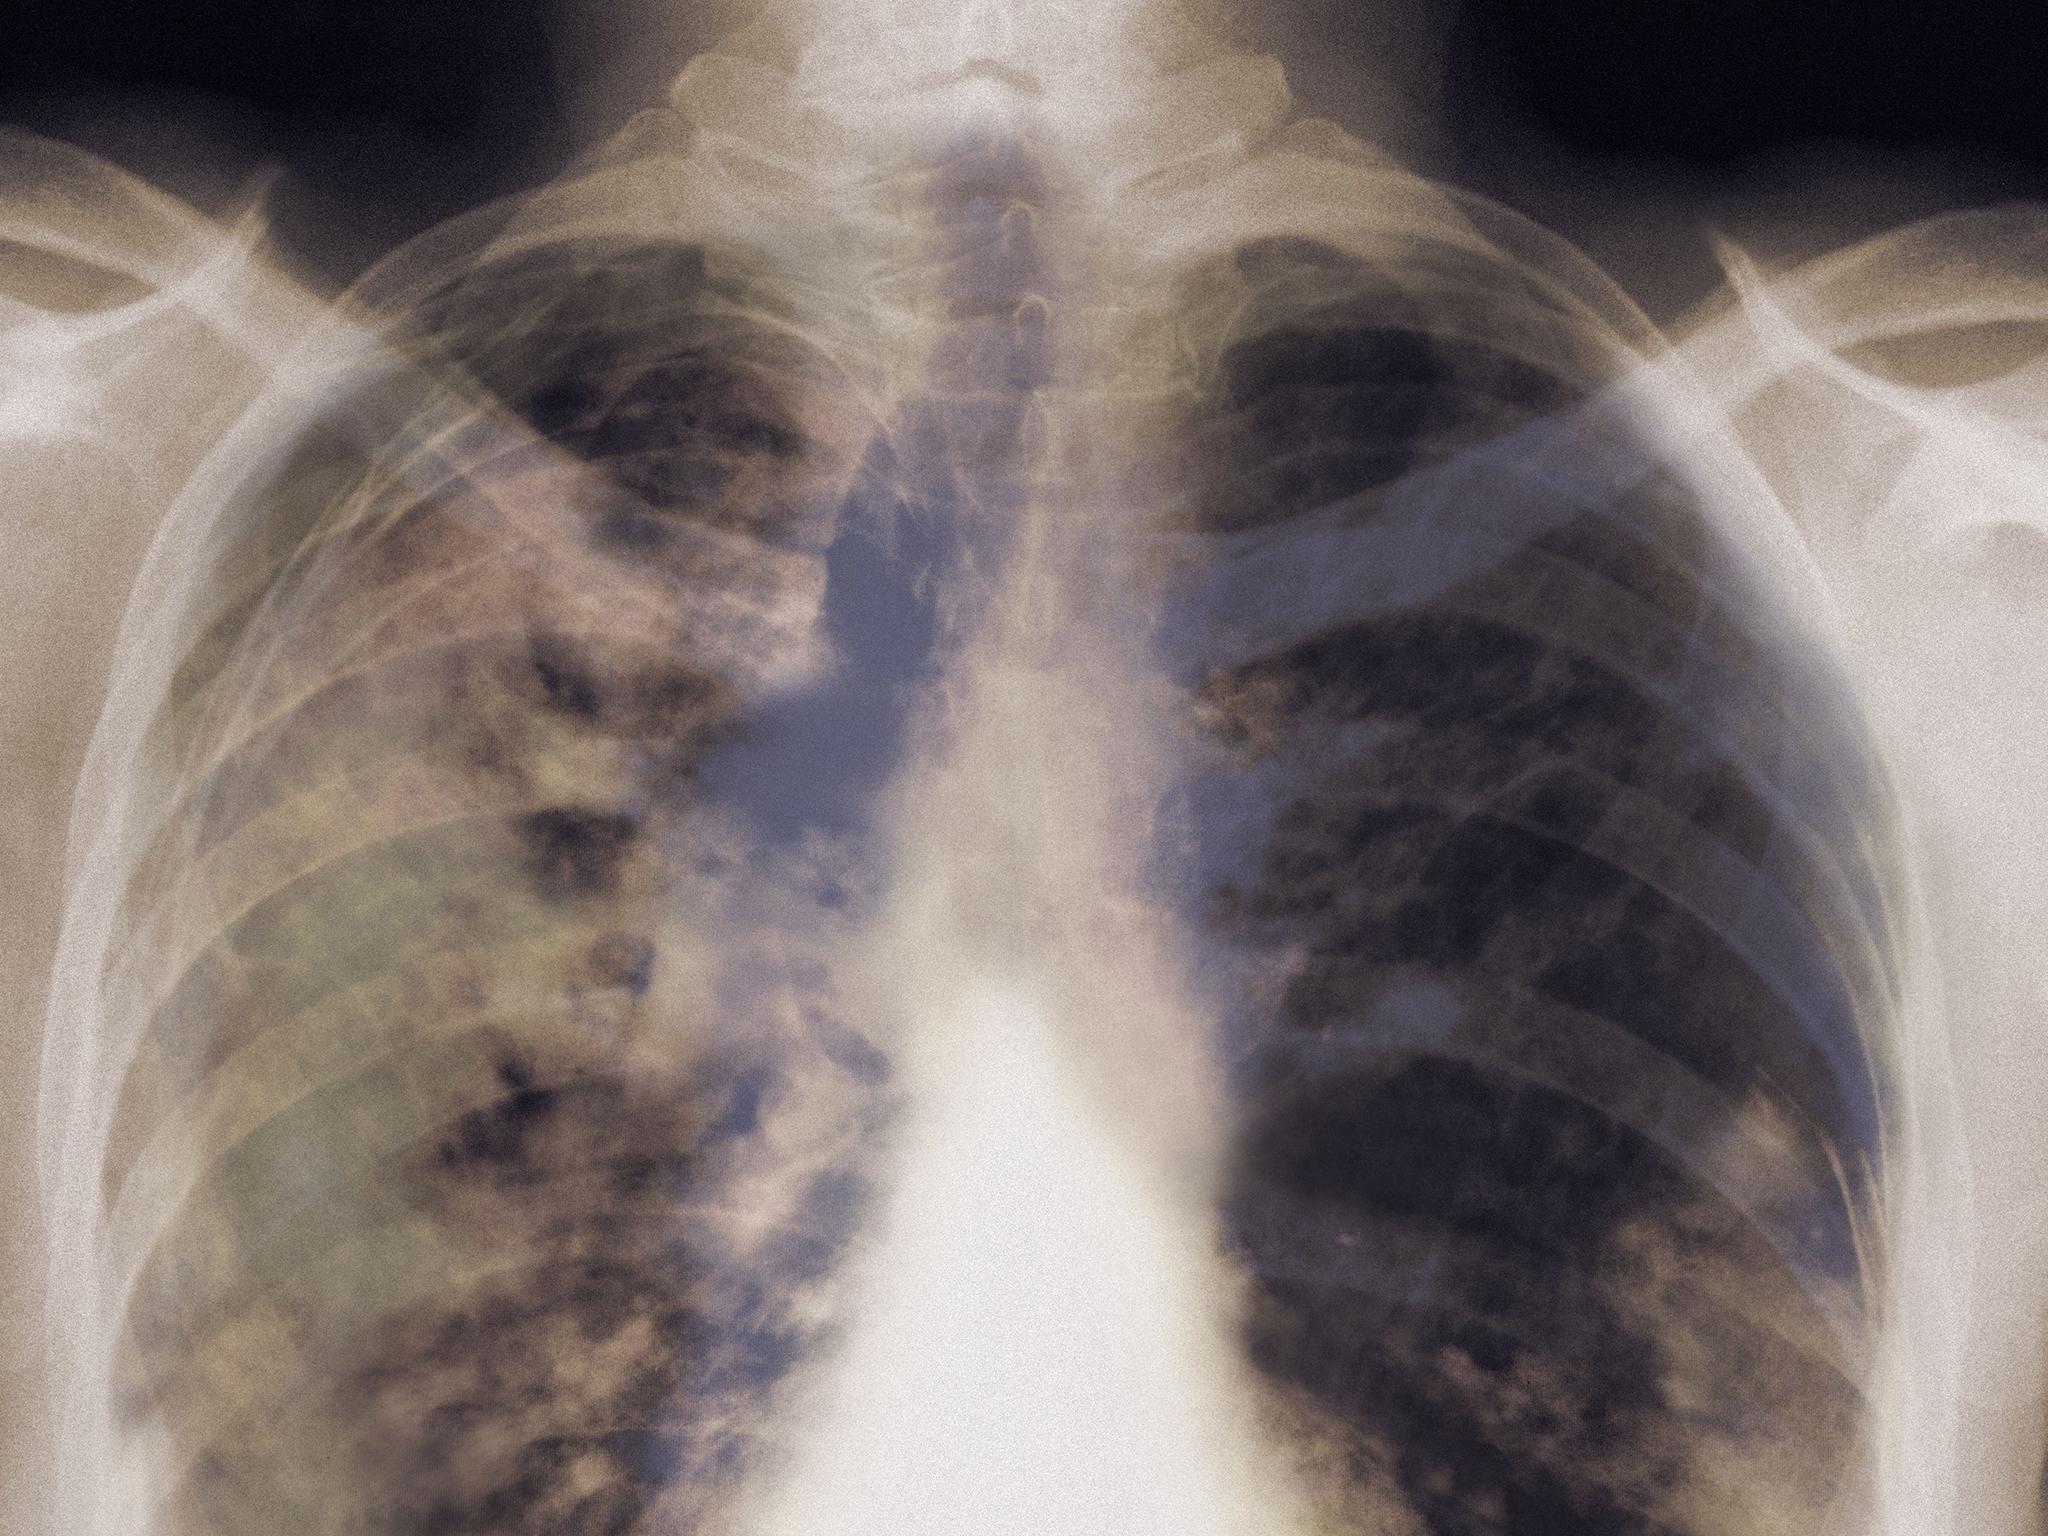

X-ray imaging provides a startling visual representation of the damage smoking inflicts on lung tissue. When comparing X-rays of healthy lungs to those of smokers, the differences are apparent even to untrained observers.

Healthy lungs appear as light, clear areas on X-rays, with visible bronchial structures. In contrast, a smoker’s lungs often show:

- Darker, mottled areas indicating tar deposits

- Increased opacity due to inflammation and fluid buildup

- Thickened bronchial walls

- Possible masses or nodules that may indicate early-stage tumors

These visual differences reflect the profound physiological changes occurring within smokers’ lungs, impacting their ability to function effectively.

Here’s what an X-ray of a normal, healthy lung looks like (left) and one of a lung damaged by smoking (right).

Even a lay person can see the difference between the two images. The damage smoking does to lung tissue is very visible. Smoke contains 4 000 chemicals, including carbon monoxide. This makes the job of the lungs much harder and oxygen can’t properly circulate through the body. The chemicals in cigarette smoke irritate and inflame the airways and lungs.

Healthy lungs are light pink, while a smoker’s lungs appear dark and mottled due to inhaled tar.

The texture of the two also differs, with damaged lungs being much harder and more brittle.